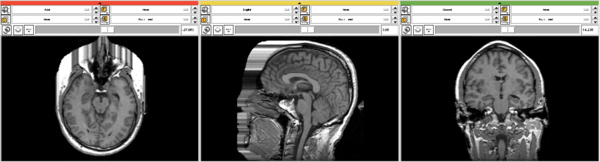

For the following example an image dataset of a human head was used.

After execution of the privacy module there is a additional surface visible on the front of the head surface.

This example shows the data in the 3D view in slicer before and after the usage of two different parameter settings in the module.

From another point of view: